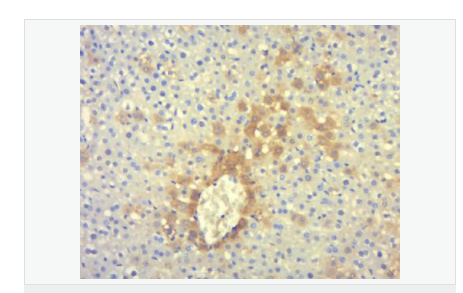

| 產(chǎn)品應用 | ELISA=1:5000-10000 IHC-P=1:100-500 IHC-F=1:100-500 Flow-Cyt=1ug/Test IF=1:100-500 (石蠟切片需做抗原修復) not yet tested in other applications. optimal dilutions/concentrations should be determined by the end user. |

| 細胞定位 | 細胞漿 |